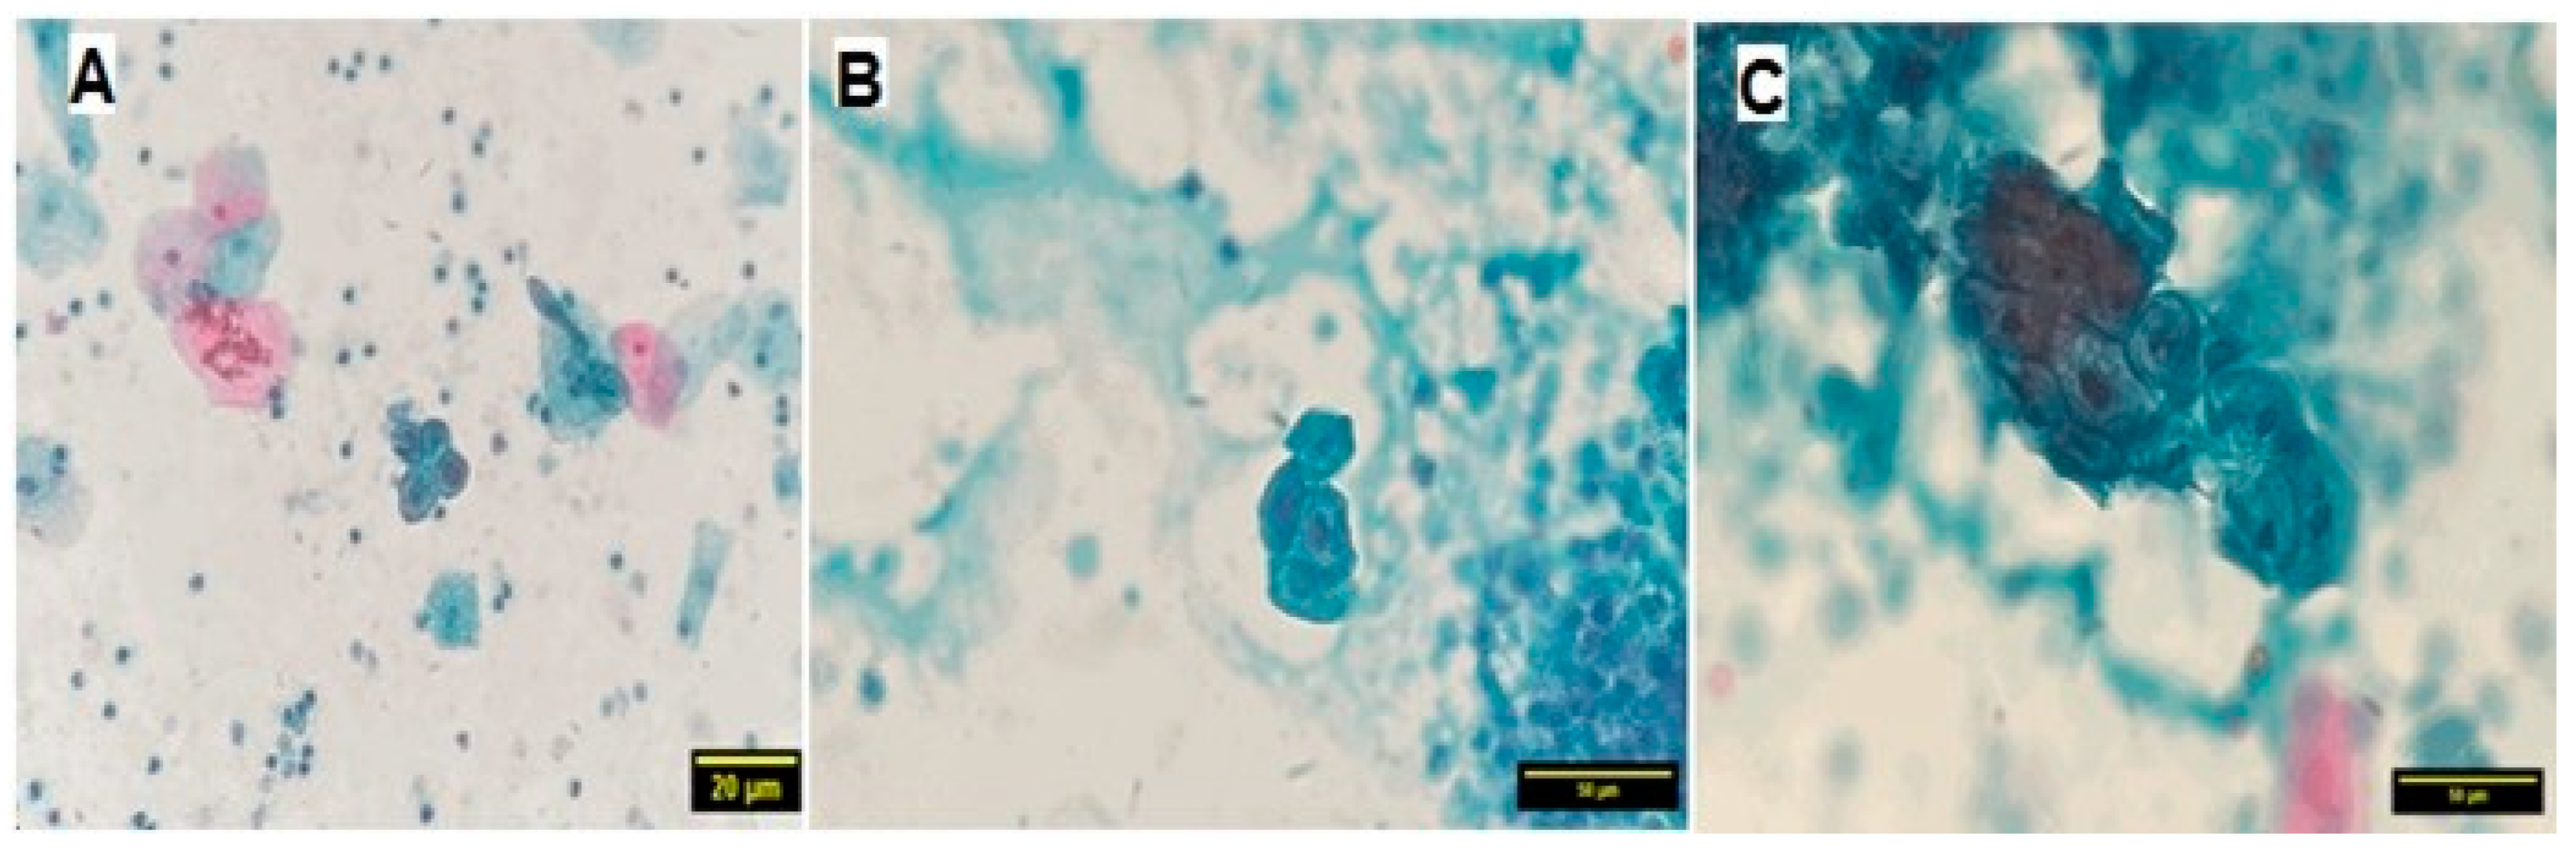

| Nuclear atypia by PAP stain | Present | 8 (16%) | 0 (0%) | 8.696 | 0.003 |

| Absent | 42 (84%) | 50 (100%) | |||